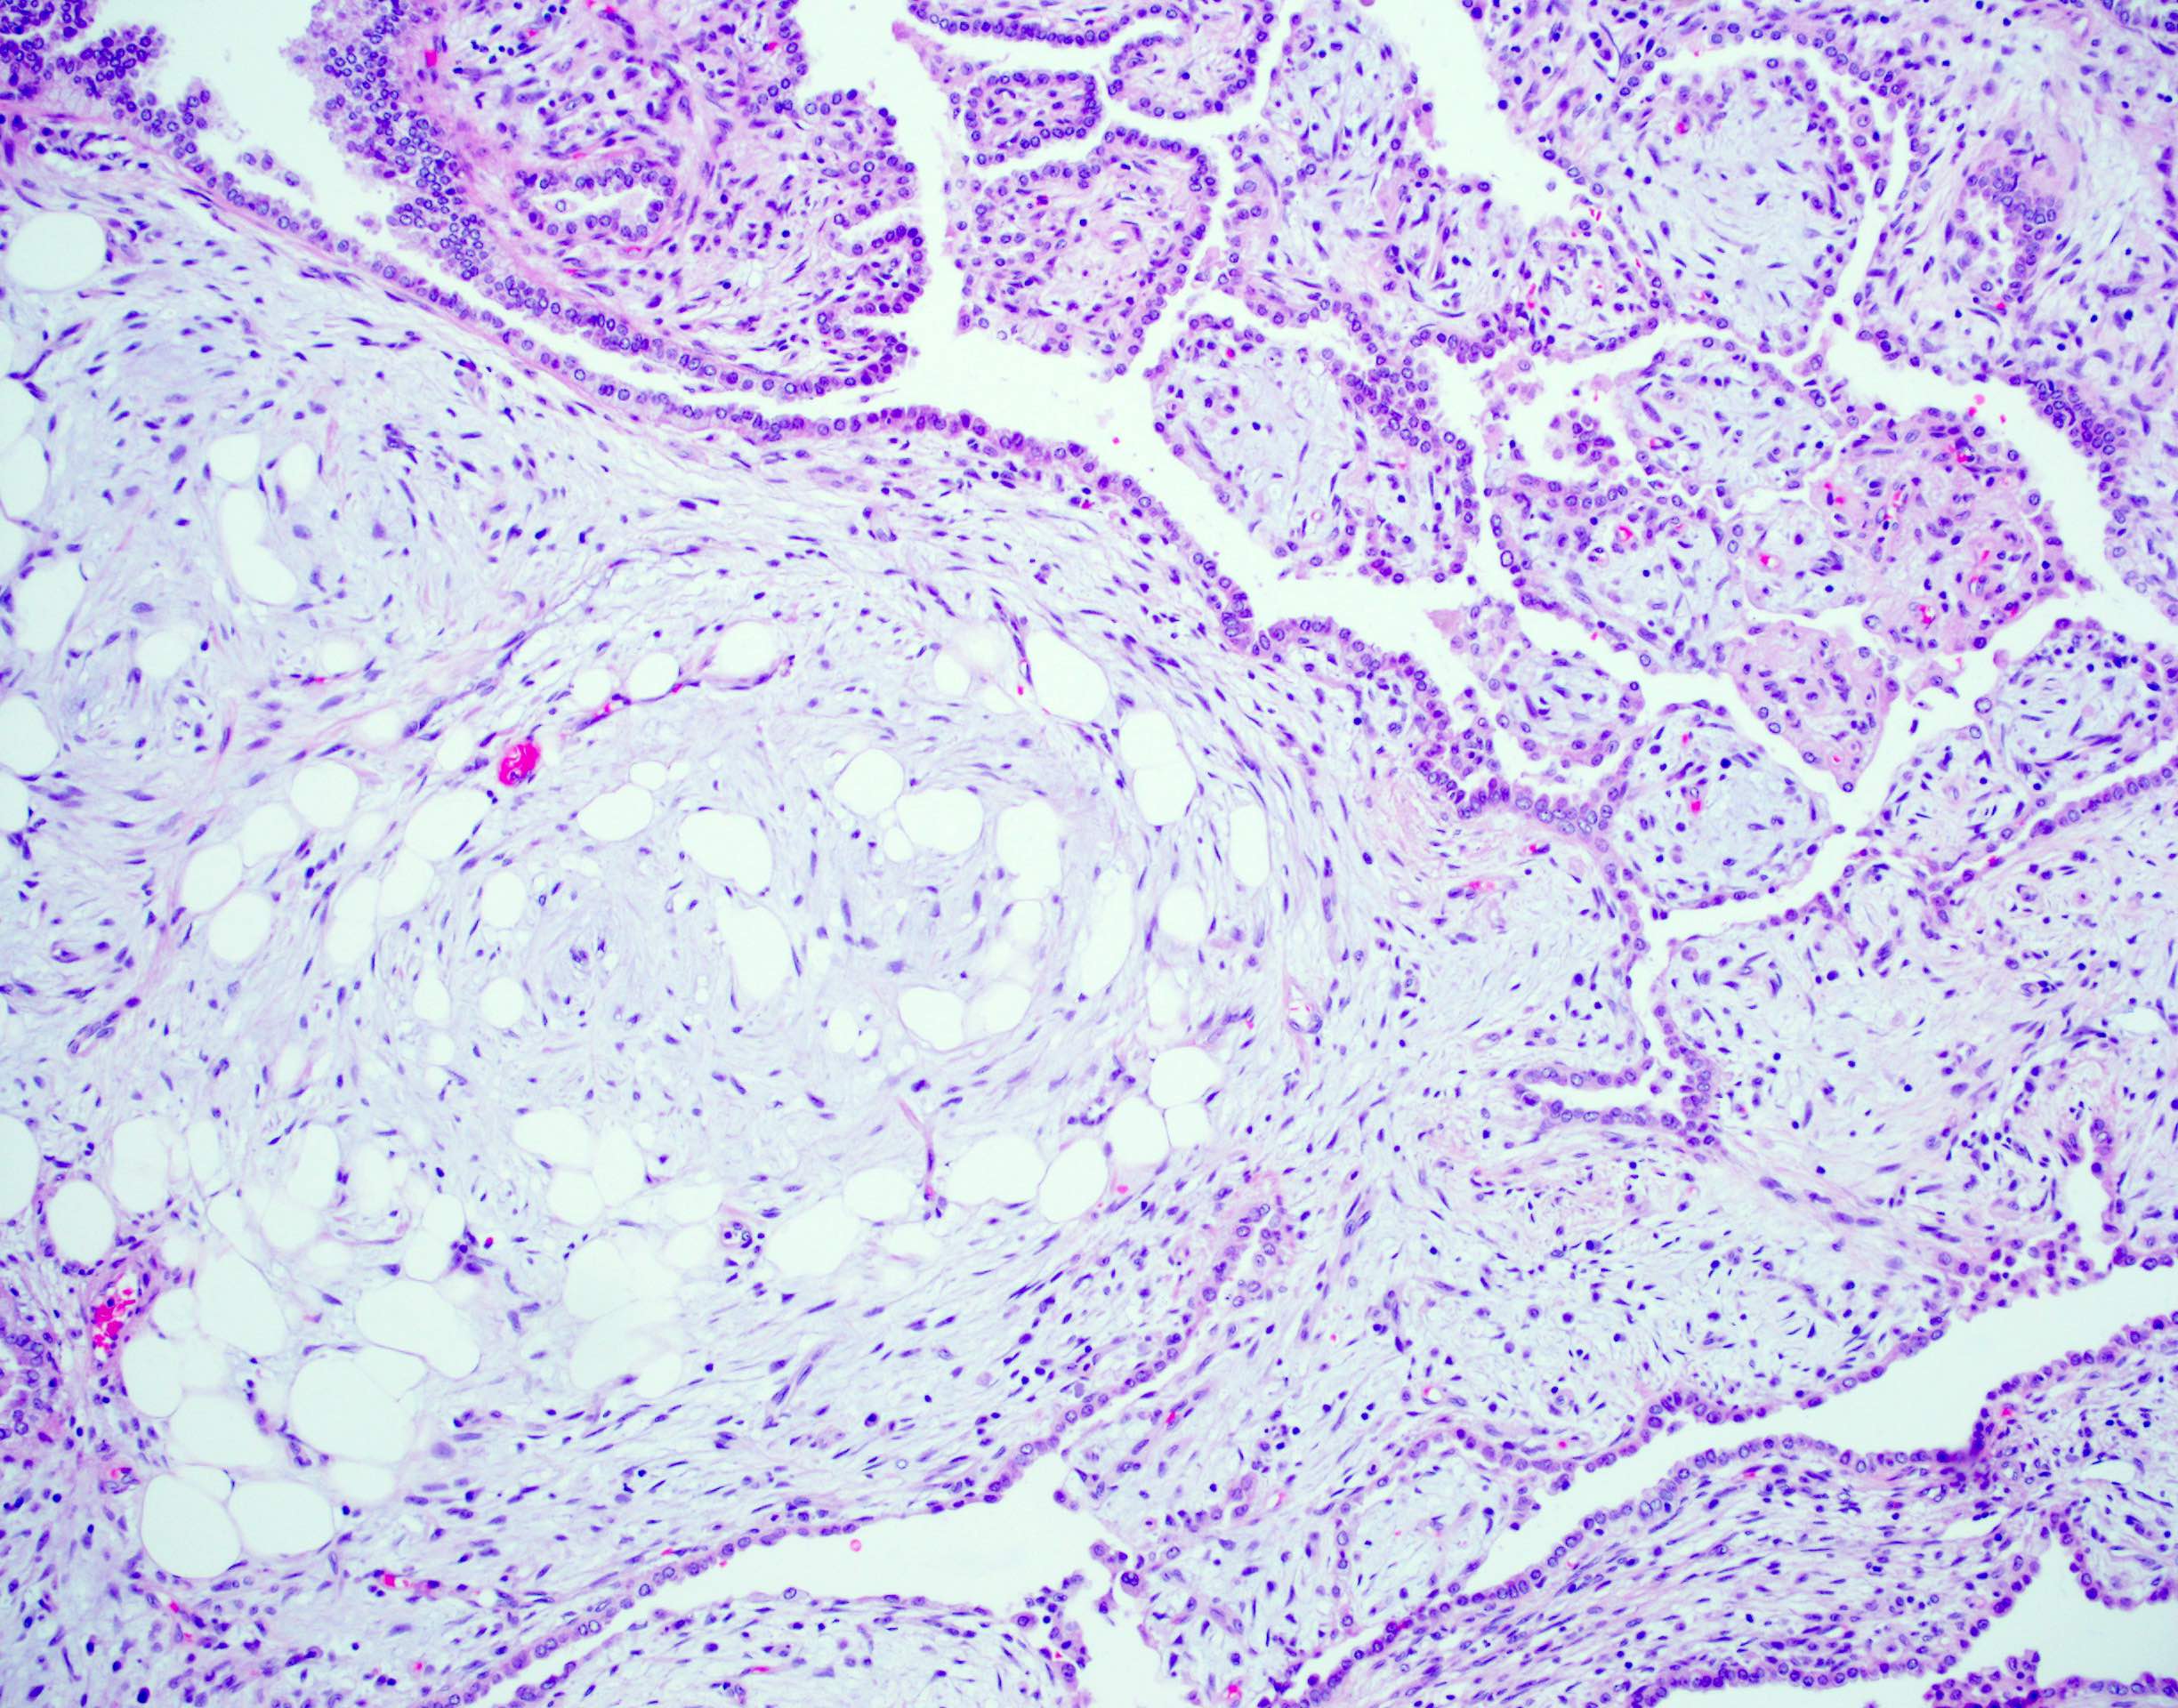

Microscopic (histologic) description

- Composed predominantly of varying degrees of mesenchymal tissue: hyaline cartilage, fat, smooth muscle and bone

- Other connective tissue elements may be present, represented by bland spindle cells, fibrous tissue or myxoid change

- Variably conspicuous, entrapped benign epithelial cells

- Reference: Thorax 1987;42:790

Microscopic (histologic) images

Contributed by Hui-Hua Li, M.D., Ph.D. and Jefree J. Schulte, M.D.

- Lung, left, needle core biopsy:

- Pulmonary hamartoma (see comment)

- Comment: The histologic sections reveal the presence of a benign pulmonary lesion composed of hyaline cartilage, fibroadipose tissue, bone and bland spindle cells in myxoid stroma. The mesenchymal elements appear to entrap benign respiratory epithelium. These findings support the above diagnosis.

- Lung, right, wedge resection:

- Pulmonary hamartoma (3.2 cm) (see comment)

- Comment: The histologic sections reveal the presence of a well circumscribed benign pulmonary lesion composed of hyaline cartilage, fibroadipose tissue, smooth muscle and bland spindle cells set in fibromyxoid stroma. The mesenchymal elements appear to entrap benign respiratory epithelium. These findings support the above diagnosis.